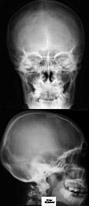

RTG głowy 14-latka.